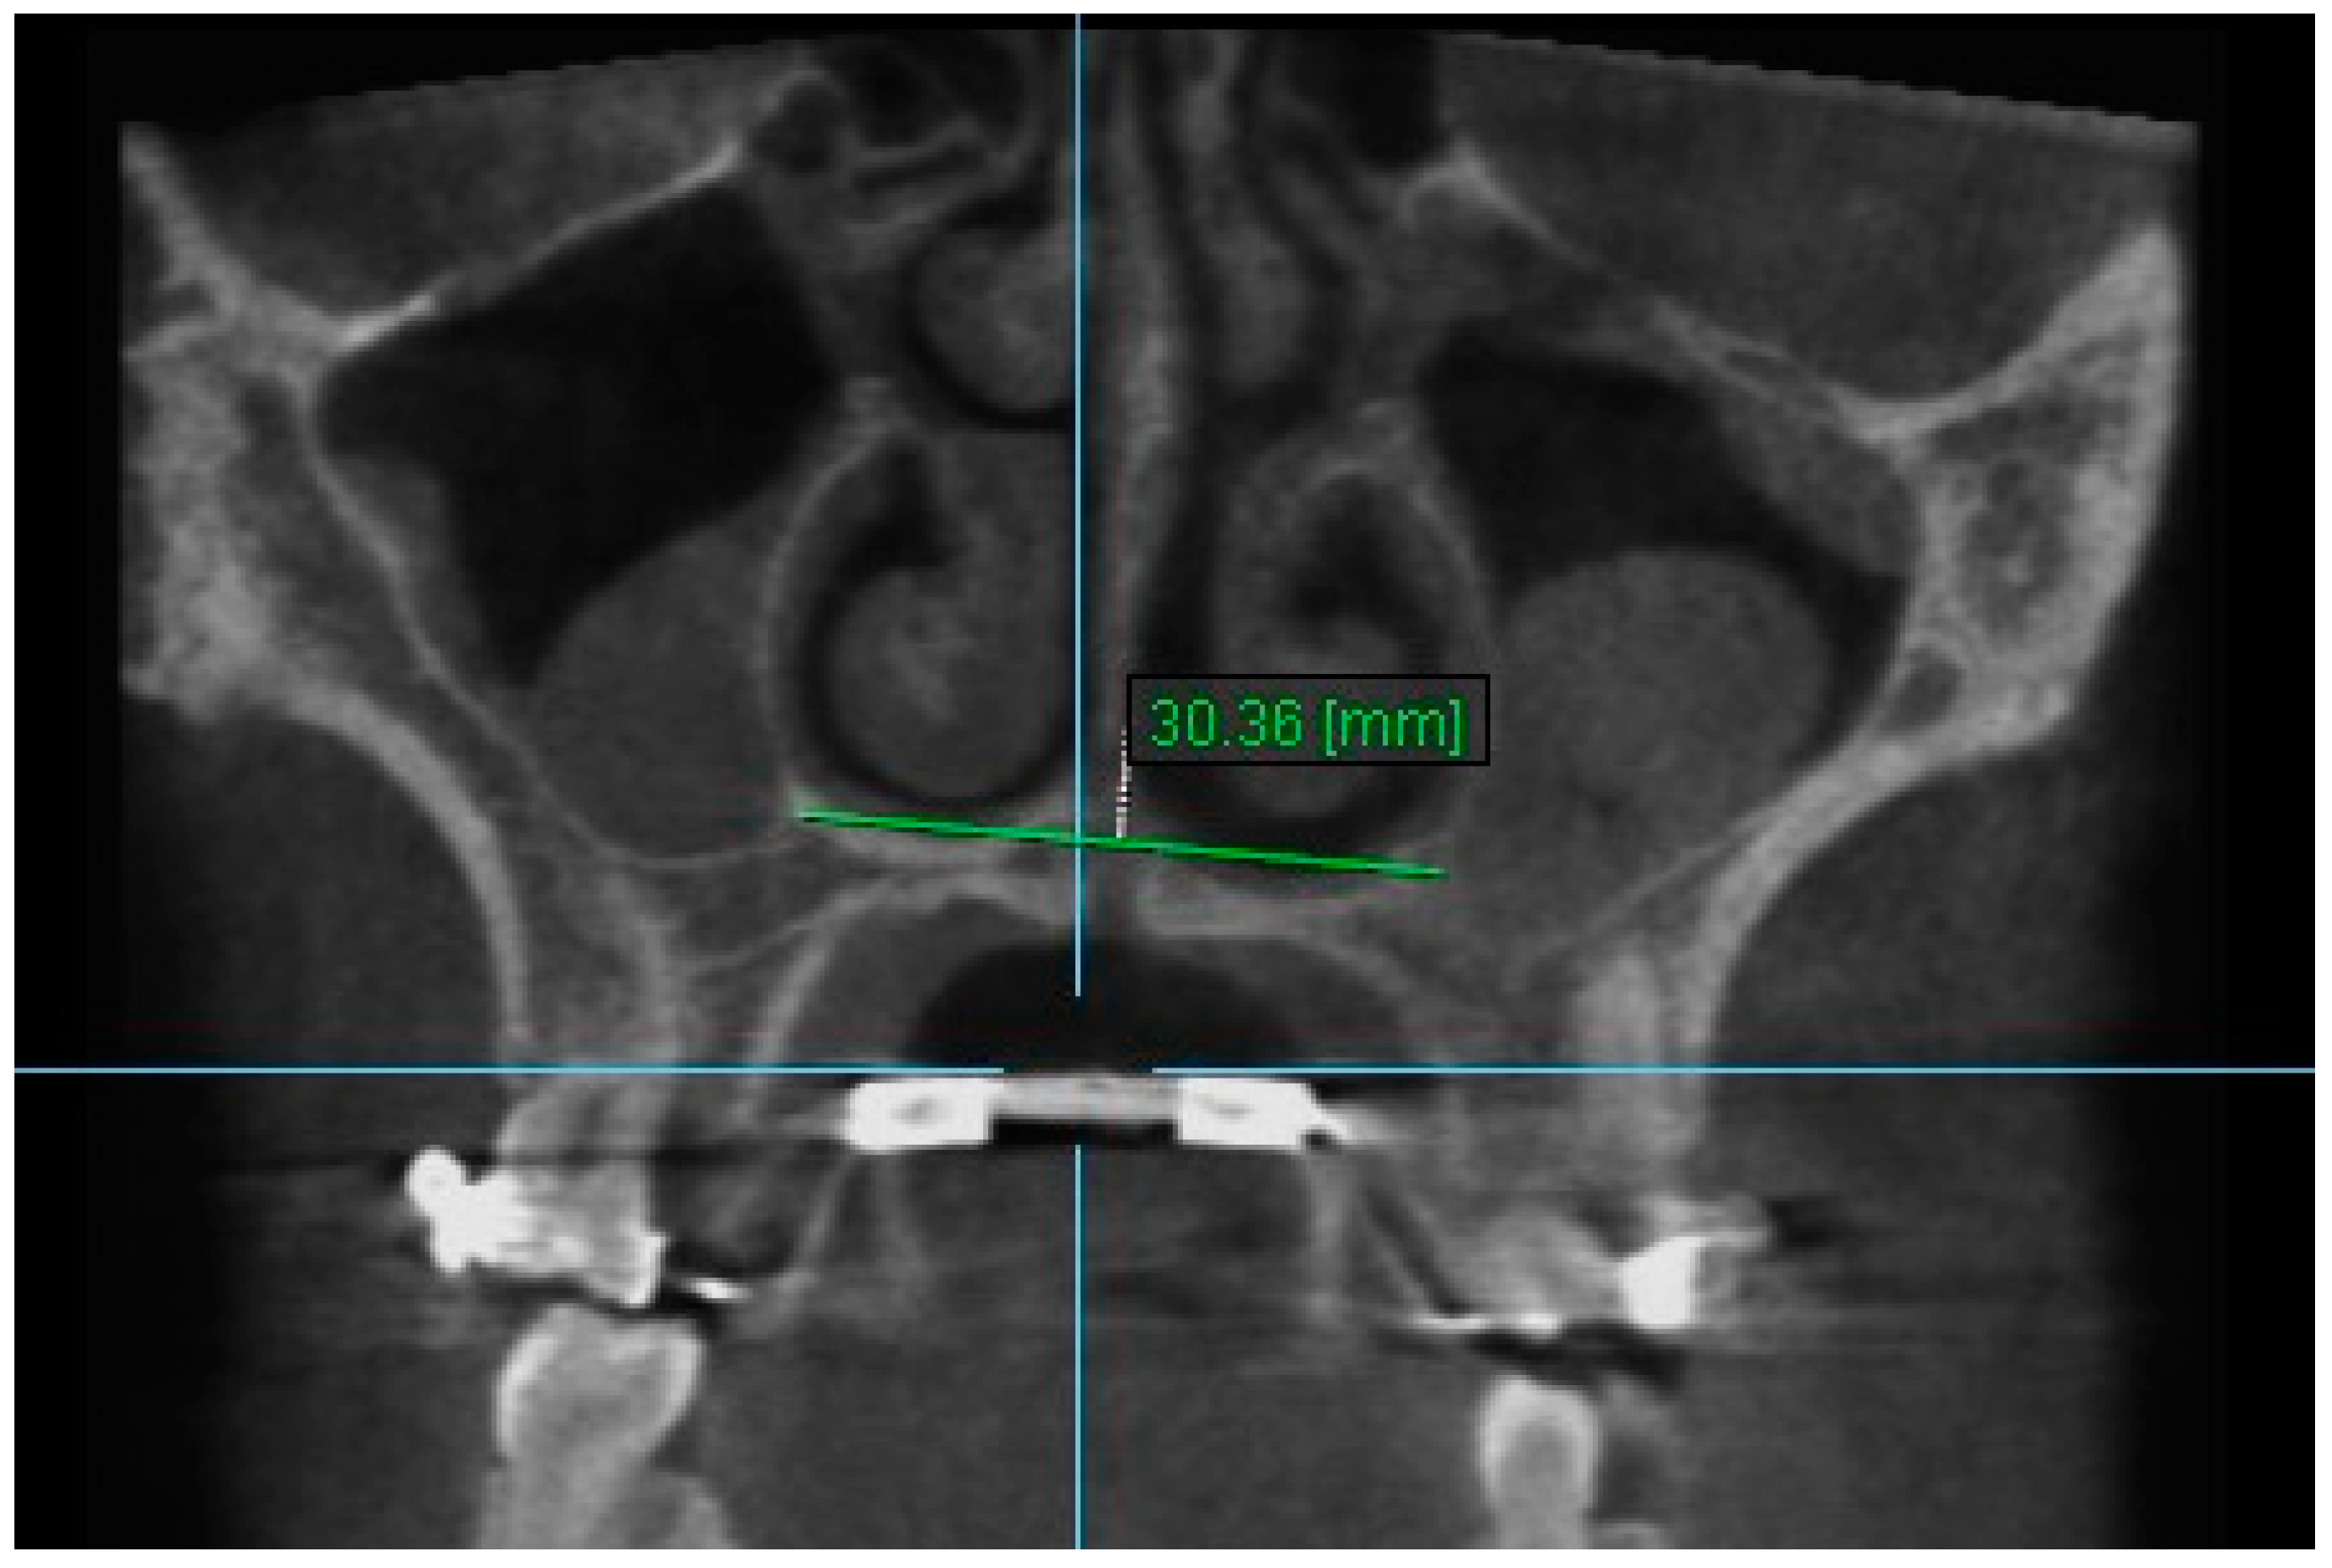

| Nasal Width 1 | T1 | 30.36 ± 2.76 | 30.44 ± 2.69 | 0.998 (0.992–0.999) |

| T2 | 32.46± 2.69 | 32.47 ± 2.57 | 0.997 (0.989–0.999) | |

| T3 | 31.71 ± 2.76 | 31.72 ± 2.77 | 0.998 (0.993–0.999) | |

| Nasal Width 1 | 28.83 | 30.97 | 30.14 | 2.13 | *** | 1.30 | *** | −0.83 | ** |